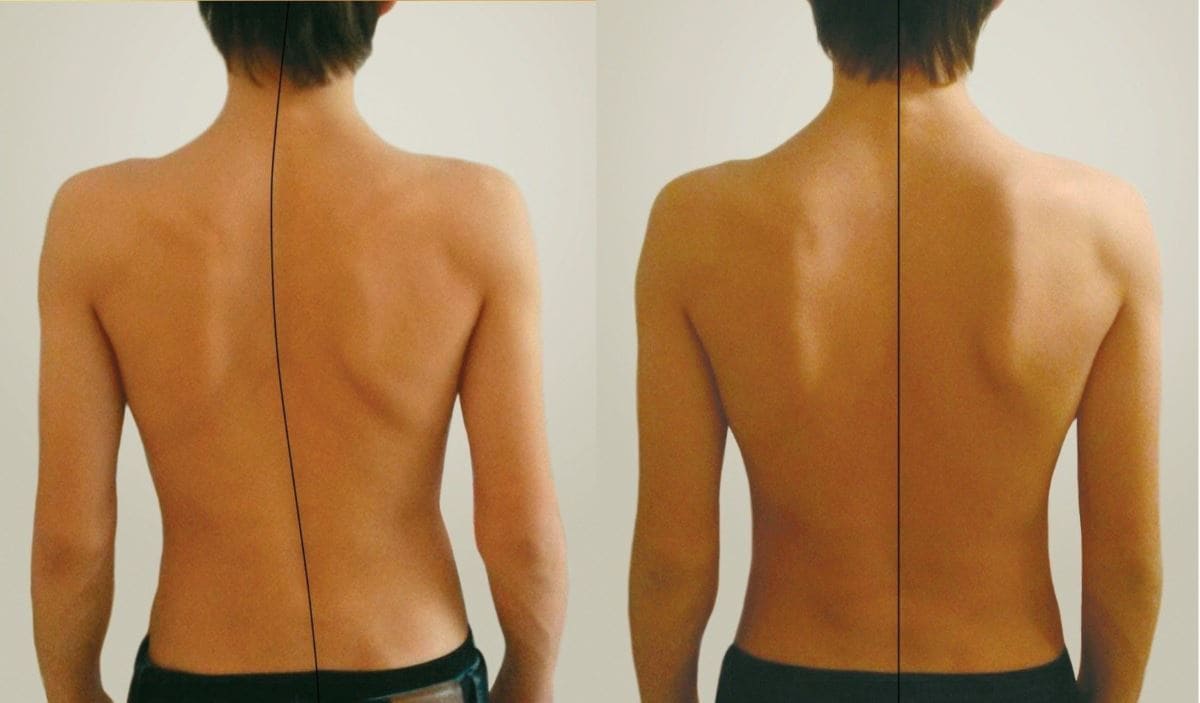

Искривление позвоночника: причины и последствия на снимках